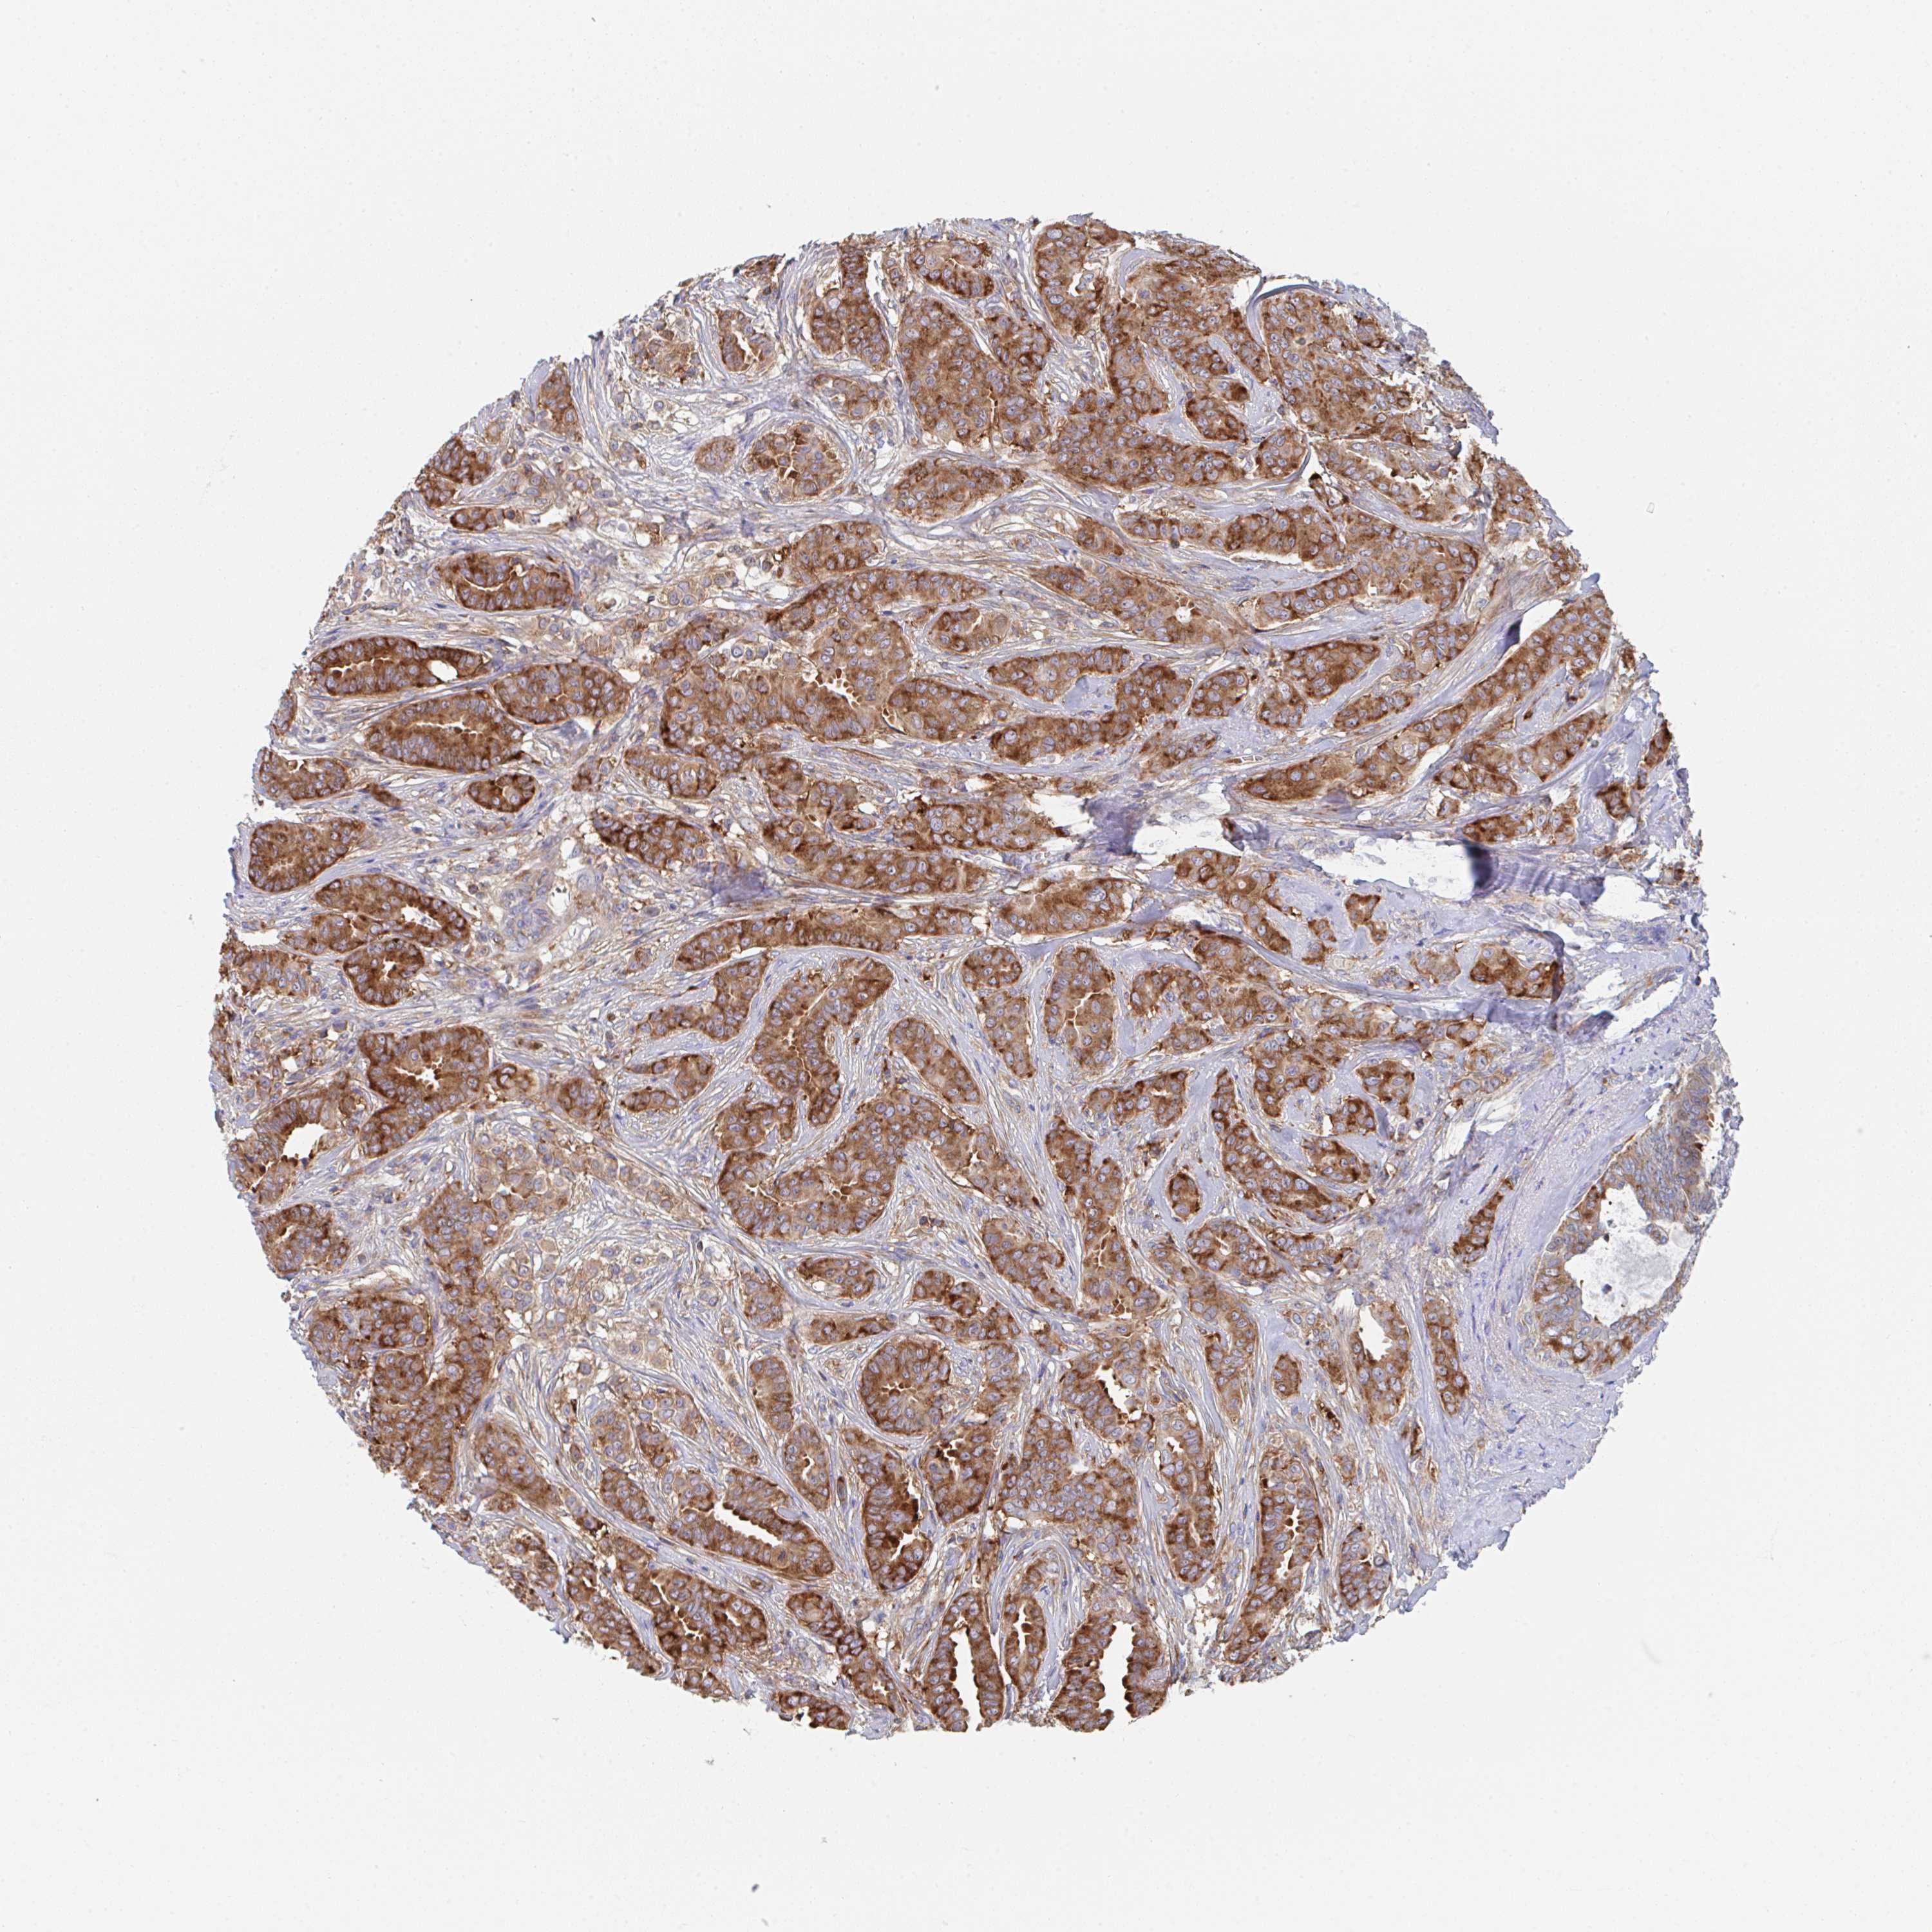

CANCER BREAST CANCER Show tissue menu

BRCA TCGA BRCA VALIDATION PROTEIN EXPRESSION